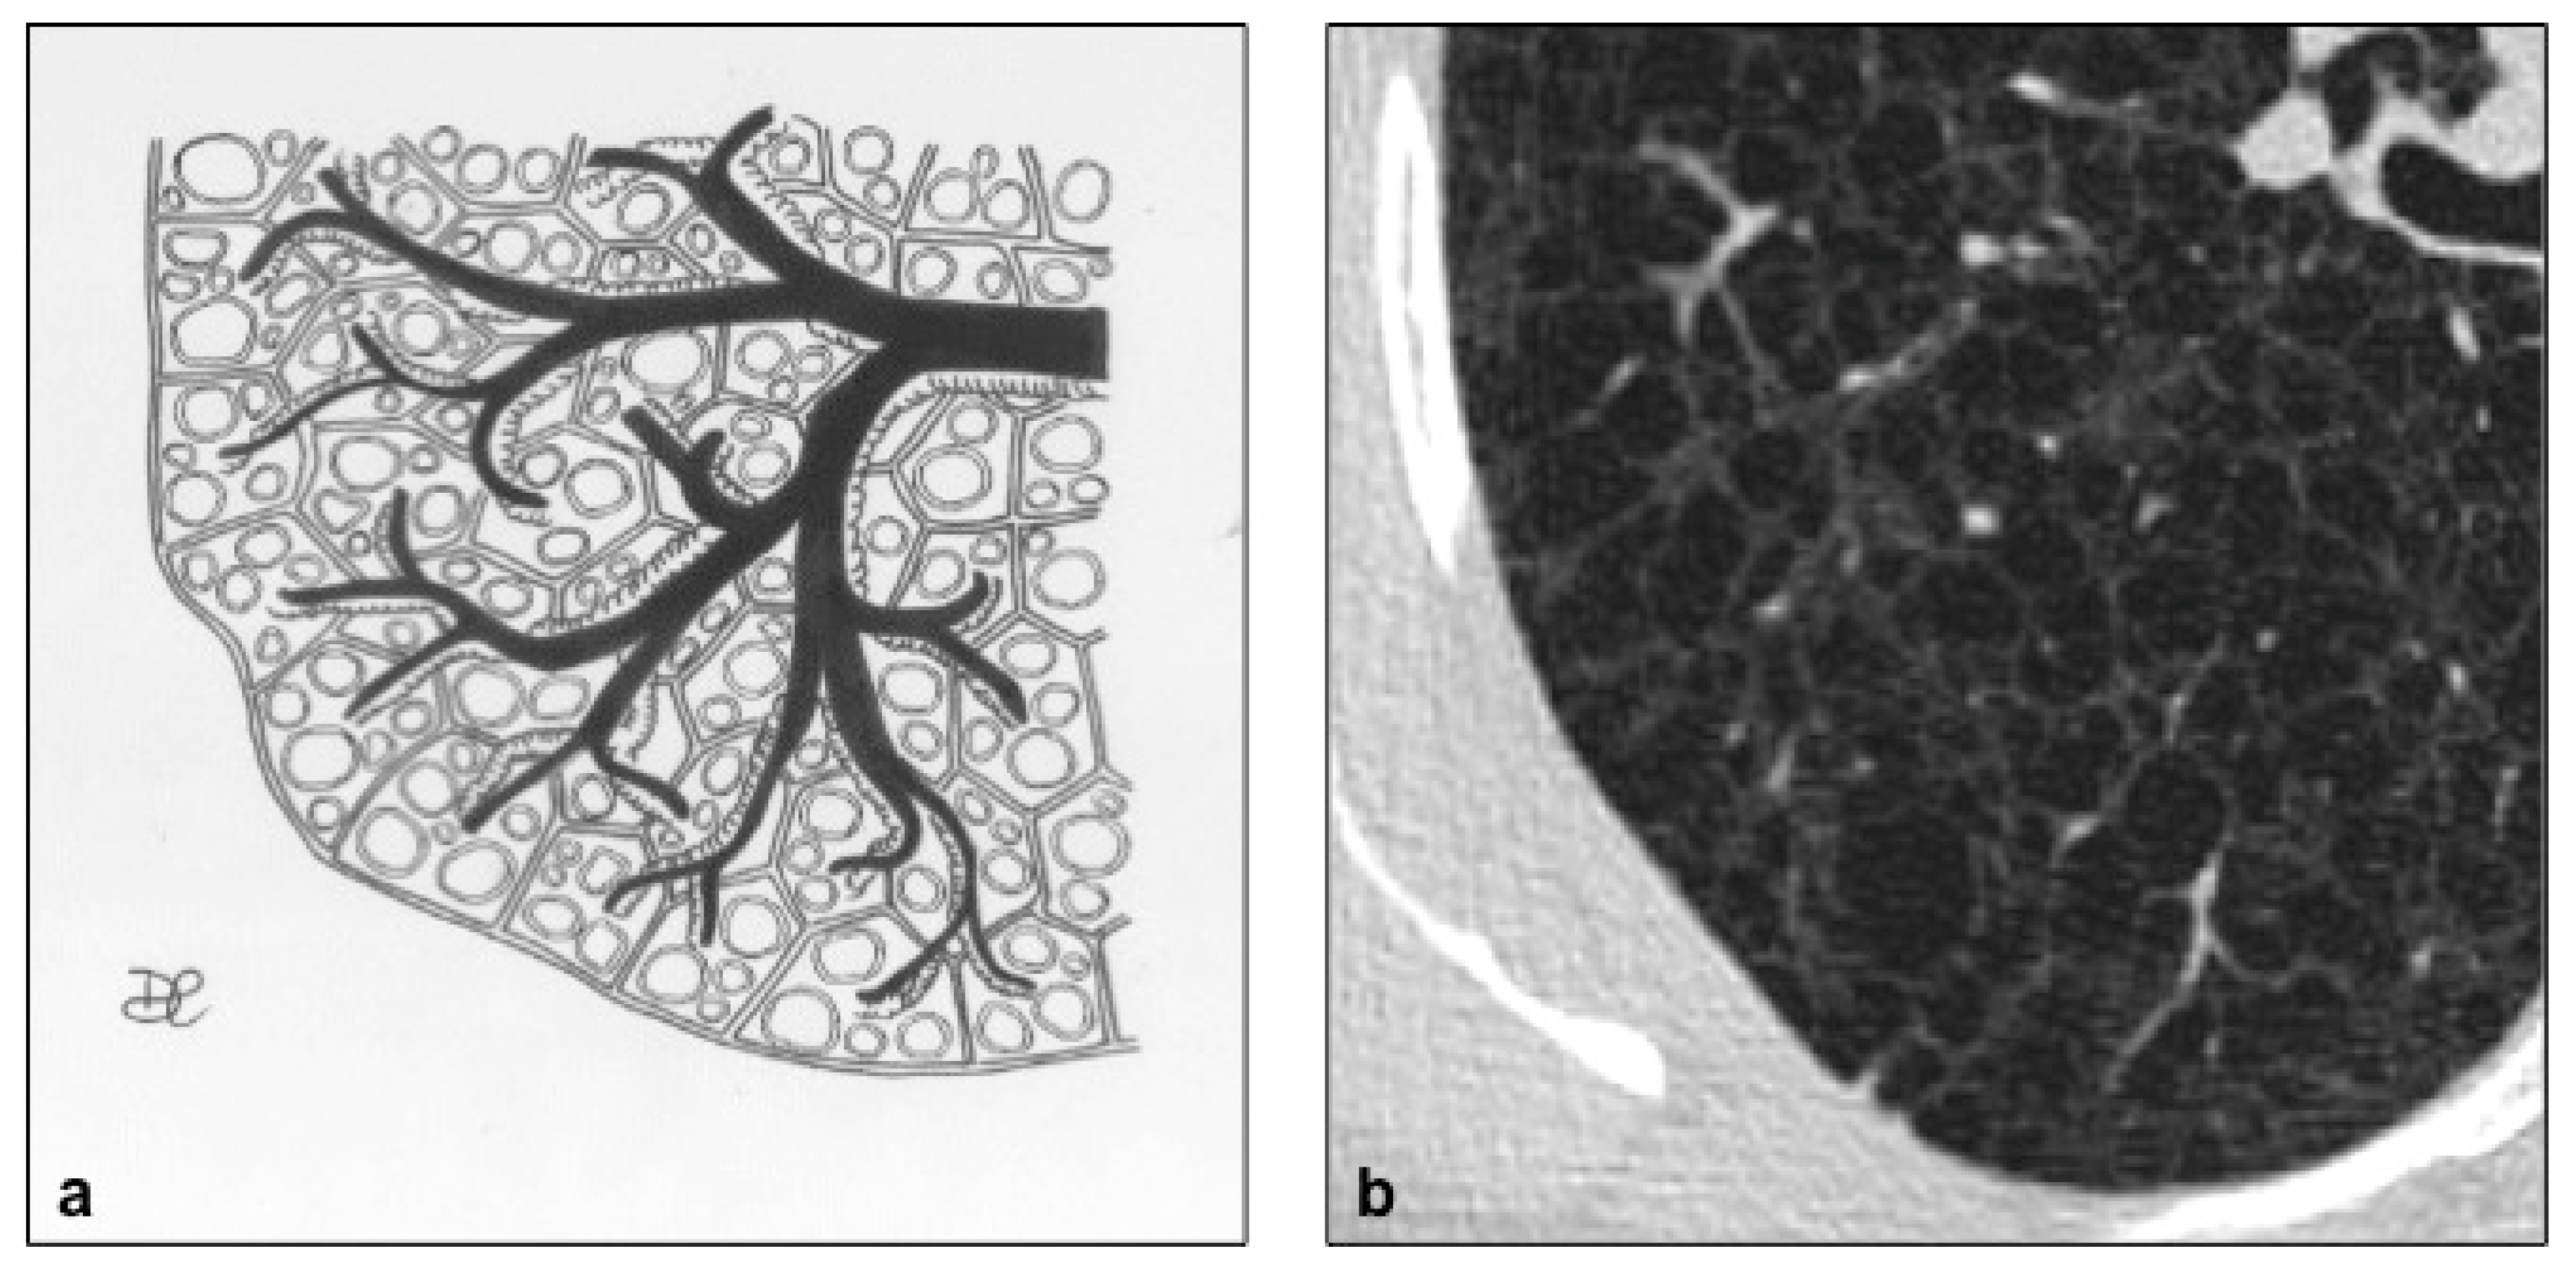

Figure 5. LAM cystic pattern (a). Lung cysts with rounded regular shape and thin walls are shown on pictures (a,b). This figure has been partially modified from ECR 2017/C-2141 Cystic pattern in lung diseases: a simplified HRCT guide based on free-hand drawings, DC Caltabiano, V. Costanzo, L. Mammino, V. Vindigni, S. Torrisi, R. Rosso, LA Mauro, C. Vancheri, S. Palmucci.

LAM occurs mostly in women of childbearing age, usually between 17 and 50 years, probably related to the role exercised by the activity of the estrogens, even if cases of prepubertal and octogenarian patients have been also described [16]. Estrogens’ role is unclear, but recent studies demonstrate that estrogenic hormones can activate protein kinase B and favor dysregulated protein translation through up-regulation of Fra1 (Fos-related antigen 1) [17]. In LAM, the development of cysts is due to focal bronchiolar dilation, caused by the proliferation of atypical hamartomatous tumor-like muscle cells in the walls of the airways, which determines a “ball-valve” effect; the progressive amount of cells into the walls narrows the lumen, leading to increased pressure, and then to dilation of bronchioles. LAM cells expand into the interstitium, in the absence of neighboring tissue invasion, but in some cases show airways, the pulmonary artery, diaphragm and retroperitoneal fat involvement, with bronchial cartilage damage, arteriolar wall destruction and pulmonary arteriolar occlusion [18]. LAM cysts are typically rounded in shape, with thin walls (Figure 5), variable diameter (small: 2–5 mm; intermediate: 1–2 cm; large: >2 cm) and ubiquitous distribution (Figure 6 and Figure 7). In later stages of the disease, cysts become larger and sometimes coalescent. Unlike LCH, the costophrenic angles involvement is pathognomonic, and there is sparing of the apical regions [19] (Figure 3); in addition, the adjacent lung parenchyma is normal, although areas of superimposed ground-glass opacities, secondary to alveolar hemorrhage or lymphatic congestion, are frequently detected [20]. Lung nodules are typically absent in LAM, a feature that helps to distinguish it from LCH. The diagnostic criteria—according to the 2016 guidelines—include characteristic HRCT findings plus at least one of the following: [21]: